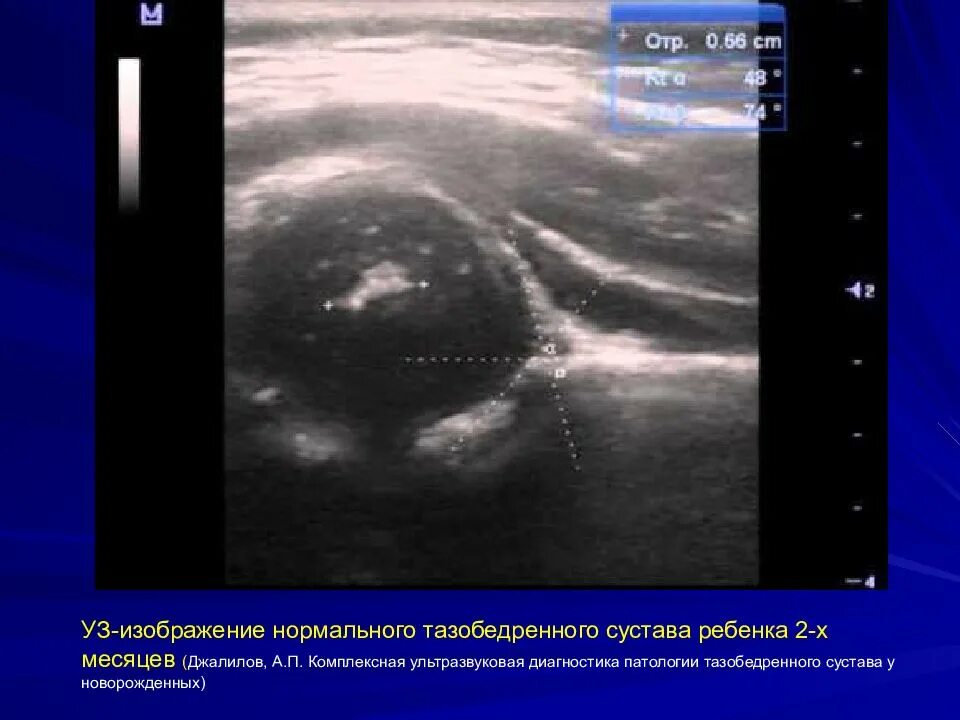

Где сделать узи тазобедренного сустава